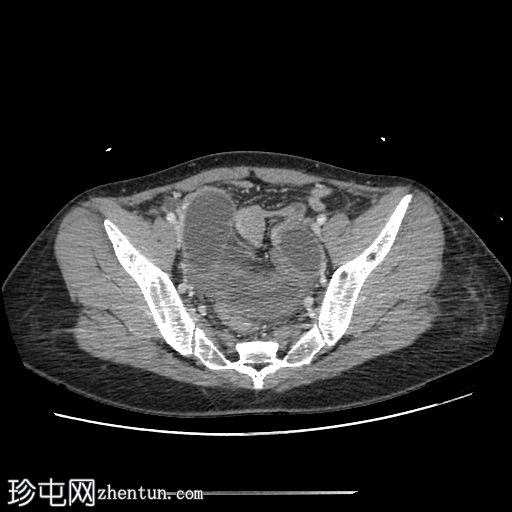

轴位增强扫描(门静脉期)

小肠袢明显扩张,左侧附件区可见双移行点,远端回肠短段闭袢梗阻,肠颈位于左侧输卵管/左侧子宫血管附近。

肠系膜血管充血,腹盆腔可见游离液体,提示肠系膜充血。

远端回肠袢和结肠已减压。

无肠缺血或穿孔的影像学证据。

CT 检查结果提示左侧附件水平小肠短段闭袢性梗阻。肠段的移行点和形态提示可能存在阔韧带或与左侧附件结构相关的粘连带引起的内疝。

剖腹探查发现一段小肠经左侧子宫阔韧带的小缺损处疝出并发生绞窄。复位绞窄的肠段后,缝合阔韧带缺损。